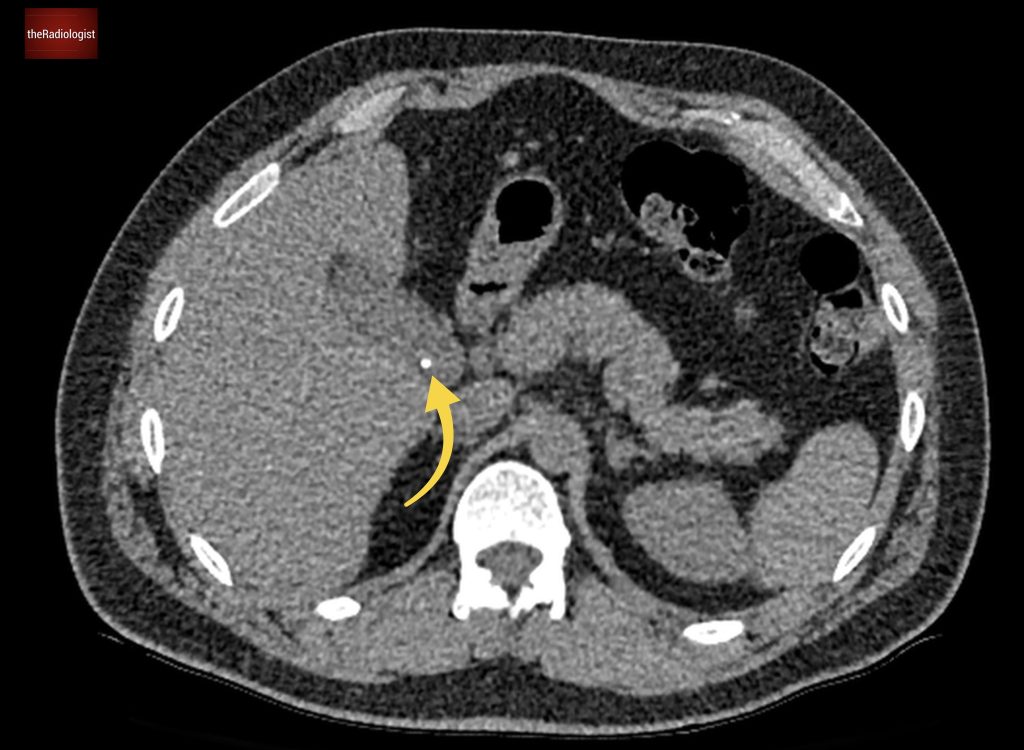

If we look at the psoas muscles on this scan below we can see there is some asymmetry . The right psoas is larger than the left and we’ve lost some of the fat planes within the muscle.

Compare the psoas muscles side by side. The right sided psoas muscle appears expanded with a loss of its normal fat planes.